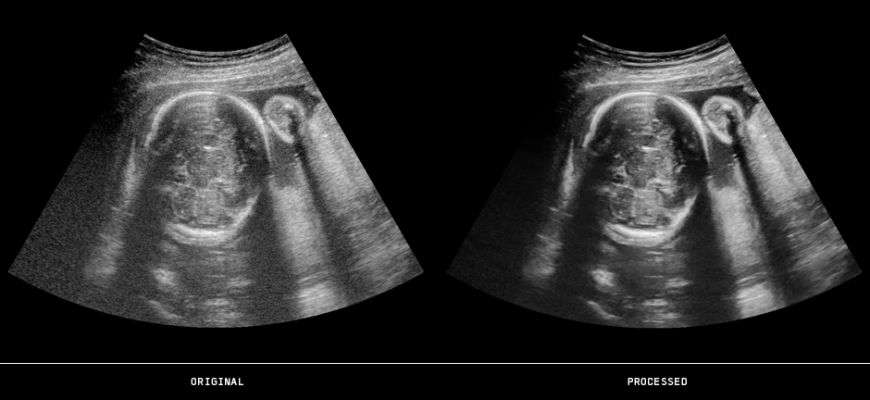

November 22, 2013 — ContextVision will debut four real-time ultrasound image enhancement packages as part of its US PlusView Family at the Radiological Society of North America Annual Meeting (RSNA 2013) in Chicago. The packages, optimized for individual application areas will ultimately provide medical professionals with enhanced diagnostic confidence. Elements of the four packages include speckle reduction, edge enhancement, efficient line connectivity and higher grayscale contrast, enabling direct, focused enrichment of selected image features.

• Women’s health: With homogenization of soft tissue as well as greater contrast and edge enhancement, imaging professionals are able to better detect lesions in soft tissue during breast examinations. For more reliable measurements of a fetus, the women’s health package provides clear lines and edge conspicuity for greater diagnostic confidence.